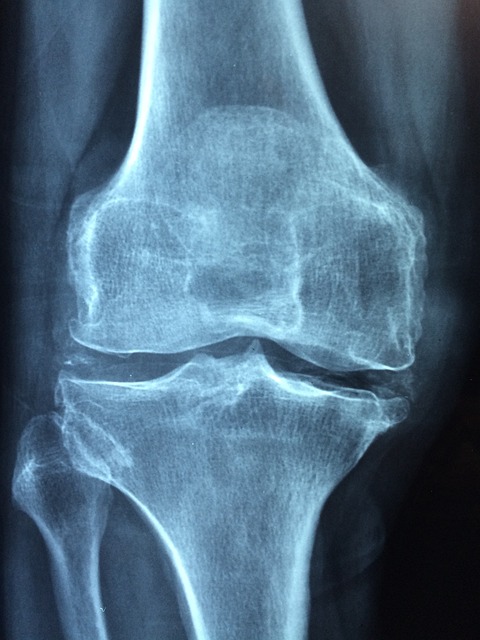

골다공증은 조용히 골밀도에 침투하여 중년 여성에게 특히 위협이 됩니다. 폐경기 동안 호르몬 변화, 특히 에스트로겐 감소가 발생하면 골밀도가 감소하여 뼈가 골절에 더 취약해집니다. 골다공증은 중년 여성에게 신체뿐 아니라 정서와 일상생활 전반에까지 영향을 미칩니다. 골밀도가 점진적으로 감소하는 것을 특징으로 하는 골다공증은 골절 위험을 상당히 높입니다. 이러한 골절은 일상생활에 심각한 영향을 미칠 수 있습니다. 가장 흔한 골절 부위로는 고관절, 척추, 손목 등이 있으며 이는 이동에 제한을 만들고 그 기능에도 영향을 미칩니다. 몸을 구부리거나, 물건을 들어 올리거나, 자신 있게 걷는 것과 같은 간단한 활동도 무리가 될 수 있습니다. 신체 건강이 약해지면 중년 여성은 더욱 조심스럽게 일상을 살아가게 됩니다. 여기에 골절에 대한 두려움은 잠재적인 통증 및 독립성 상실과 더해져 불안과 정서적 고통을 유발합니다. 한때 활발하게 활동했던 자신이 조심스럽고 불안한 상황에 놓여있다고 생각하면 자신감이 떨어지고 우울하게 됩니다. 정서적 탄력성은 이러한 보이지 않는 어려움에 정면으로 맞서는 데 중요한 요소가 됩니다. 또한 골다공증은 즉각적인 신체적, 정서적 문제를 넘어서는 생활방식의 변화와 적응을 필요로 합니다. 중년 여성은 움직이는 방식부터 운동과 영양에 이르기까지 많은 일상의 습관을 재평가하게 됩니다. 이전에는 아무 생각 없이 즐겼던 운동을 못하게 되거나 변화가 필요할 수도 있습니다.

튼튼한 뼈의 기본은 그것을 만드는 영양을 선택하는데서 시작됩니다. 필수 미네랄인 칼슘은 뼈 형성과 밀도에 중요한 역할을 합니다. 중년 여성은 유제품, 잎채소, 견과류, 시리얼 등 칼슘이 풍부한 식품을 먹도록 해야 합니다. 비타민 D는 칼슘 흡수를 촉진하며 햇빛을 쬐는 것 또한 여전히 좋은 천연 공급원입니다. 이러한 영양소 사이의 균형은 신체가 뼈 강도를 유지하도록 도와줍니다. 이것은 단순히 영양소를 다양하게 섭취하는 것이 아니라 전반적인 건강 생활에 기여하는 음식으로 자신의 몸을 지키고 키우는 것입니다. 걷기와 계단 오르기 등을 하는 것은 골다공증 예방을 위한 확실하고 강력한 전략입니다. 이러한 운동은 뼈 형성을 자극하고, 골밀도를 향상하며, 전반적인 뼈 강도에 기여합니다. 신체의 힘과 회복력을 맛보고 감각을 키울 수 있는 기회입니다. 중년 여성은 운동의 장점과 자신이 좋아하는 활동에 참여하는 즐거움을 더해 일상에 활력을 불어넣는 선택을 할 수 있습니다. 정기 검진과 조기 개입 또한 아주 중요합니다. 정기적인 검진은 골다공증을 예방하고 잠재적 위험을 조기에 해결하는 데 핵심적인 역할을 합니다. 폐경기 여성에게 권장되는 골밀도 검사는 개인의 뼈 건강에 대해 정확한 정보를 제공합니다. 이러한 검사를 기반으로 골밀도를 보존하고 골다공증 진행을 완화하기 전략을 세울 수 있습니다. 중년 여성은 검진과 건강 평가에 적극적으로 참여함으로써 뼈 건강에 대해 필요한 지식을 스스로 습득할 수 있습니다.

골다공증 치료의 방법 중 하나는 뼈 손실을 늦추고 골밀도를 높이는 것을 목표로 하는 약물 치료와 관련이 있습니다. 알렌드로네이트, 리세드로네이트 등의 비스포스포네이트가 일반적으로 처방됩니다. 이러한 약물은 뼈 흡수를 억제하여 뼈 강도를 향상합니다. 호르몬 요법, 특히 에스트로겐 또는 에스트로겐과 프로게스틴의 조합은 골밀도를 유지하는 데 도움이 되므로 특히 폐경기 여성의 경우 또 다른 옵션입니다. 약물 치료 외에도 생활 습관 개선은 골다공증 치료에 없어서는 안 될 요소입니다. 예방을 위한 방법과 같이 걷기, 조깅, 저항력 훈련과 같은 규칙적인 체중 부하 운동을 하고 칼슘과 비타민 D가 풍부한 균형 잡힌 식단을 섭취하는 것은 치료에도 빠질 수 없습니다. 의료 전문가와 지역 사회 등 지원 네트워크는 함께 골다공증을 헤쳐나가는 동반자가 됩니다. 골다공증은 단순 의학적 개입 이상의 것이 필요하다는 것입니다. 이를 위해서는 신체적, 정서적 측면을 모두 다루는 전체적인 접근 방식이 필요합니다. 교육 자원과 지원 네트워크에 적극적으로 참여함으로써 개인은 골다공증으로 인한 문제를 이해하는 정보를 얻을 수 있고 함께 하는 커뮤니티를 찾을 수 있으며 마음의 위안도 얻을 수 있습니다.